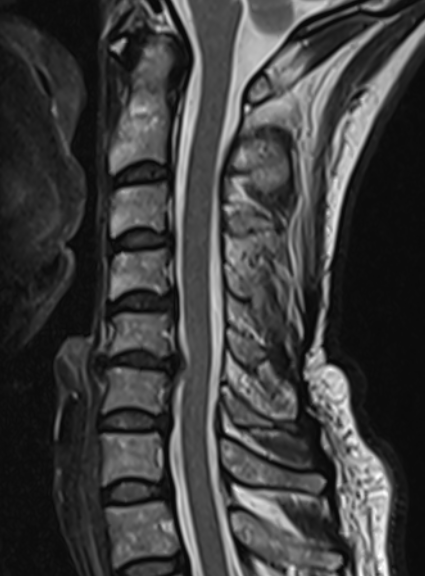

3. Disc osteophyte protrustion C5-C6